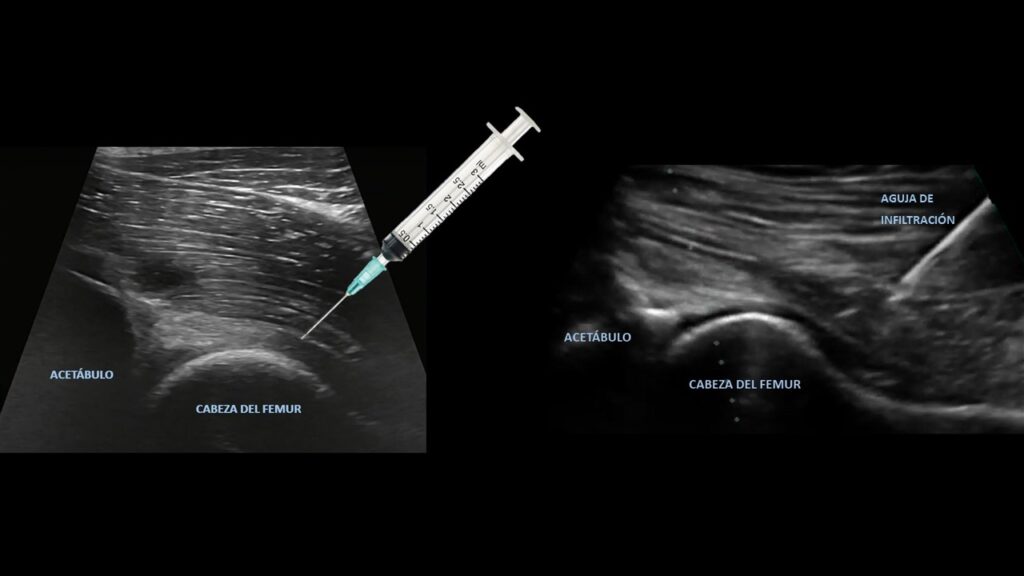

Además de estas medidas, el empleo de infiltraciones puede ayudar disminuir el dolor. Hay varios tipos de infiltraciones que pueden realizarse bajo control ecográfico, lo que permite introducir el fármaco en el punto exacto que deseamos.

Tipos de infiltraciones

-Corticoide + anestesia:

Consiste en introducir un antiinflamatorio junto con anestesia local en la rodilla. El problema de estas infiltraciones es que numerosos estudios han demostrado que pueden provocar daño al cartílago articular por toxicidad, por lo que hay que ser cuidadosos a la hora de ponerlas.

-Ácido Hialurónico:

Esta terapia se basa en dos efectos del fármaco. Por un lado, presenta capacidad antiinflamatoria, lo que ayuda a que sustancias generadas en a causa de la enfermedad de la artrosis dejen de afectar negativamente a nuestra cadera. Por otro lado, funciona como un lubricante favoreciendo la movilidad de la articulación.

– Terapias biológicas/regenerativas:

Las más empleadas son el plasma rico en plaquetas o PRP y las células madres mesenquimales. Funcionan como antiinflamatorios y se estudia su efecto sobre la capacidad de regeneración del cartílago articular y estructuras periarticulares.